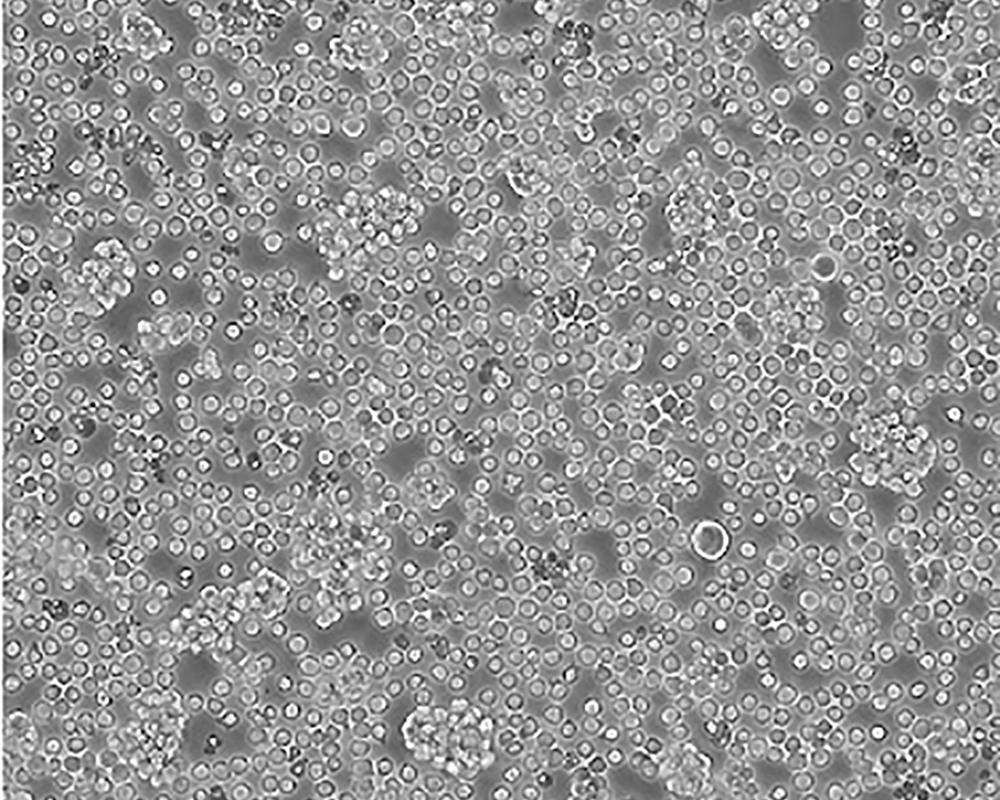

Jurkat, Clone E6-1 [Jurkat E6-1]

人T淋巴細(xì)胞白血病細(xì)胞

急性T淋巴細(xì)胞白血病;男性

Homo sapiens, human

生長特性

suspension

lymphoblast

1:2-1:4

該細(xì)胞是Jurkat-FHCRC細(xì)胞株(Jurkat細(xì)胞株的衍生)的一個克隆。Jurkat細(xì)胞株來源于一個14歲男孩的外周血。經(jīng)佛波酯和外源凝集素或抗T3單克隆抗體誘導(dǎo)后可產(chǎn)生大量IL-2(IL-2的產(chǎn)生需兩種類型的誘導(dǎo)劑);表達T細(xì)胞受體、CD3